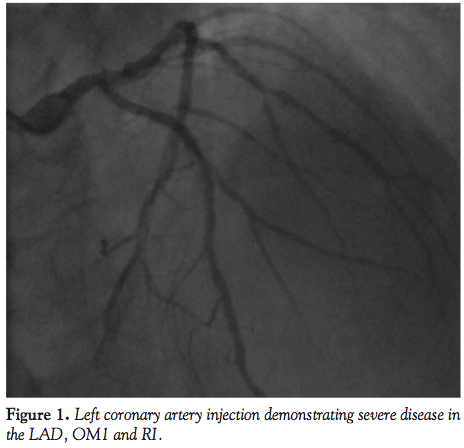

was begun, and a 6 Fr radial-specific diagnostic catheter (Tiger catheter, 6 Fr, 100 cm length; Terumo Medical Corporation) was guided to the ascending aorta by an angled tip hydrophilic wire (Stiff Angled Glidewire, 0.35 cm diameter, 145 cm length; Terumo Medical Corporation). Left coronary artery injection revealed in-segment restenoses of the proximal and mid portions of the left anterior descending artery (LAD), as well as severe obstructive disease at the origin of the first obtuse marginal branch (OM1) of the left circumflex artery (LCX) and ramus intermedius artery (RI) (Figure 1). The right coronary artery demonstrated mild diffuse disease throughout. He underwent PCI of the mid LAD, RI, and OM1 vessels. The diagnostic catheter was exchanged for a guiding catheter (Mach 1 FCL 3.5, 6 Fr; Boston Scientific) over a 300-cm long, 0.035-cm diameter J-tip wire. Adjunctive anticoagulation therapy was administered with a standard, weight-based bivalirudin bolus and infusion, and prasugrel was given orally. Activated clotting time was 352 seconds at 5 minutes after bivalirudin injection. Successful PCI was performed with deployment of a DES in the RI and percutaneous transluminal coronary angioplasty (PTCA) of the OM1 and LAD lesions.